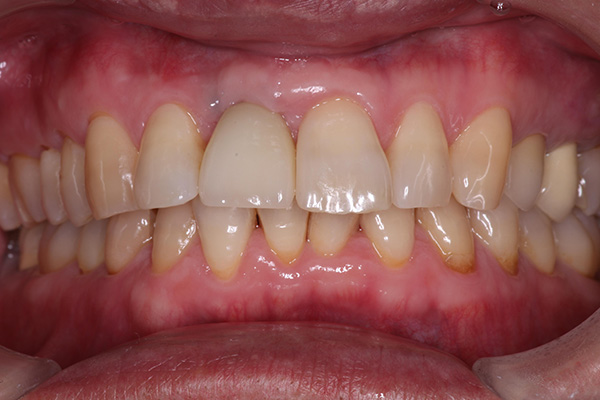

6. 術前術後の比較

右上の犬歯の見た目・機能を回復することができました。また歯周病治療により歯肉の炎症が改善されました。